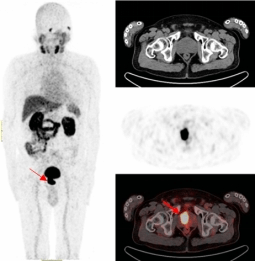

既无肉眼血尿,又无排尿异常,更没有腰酸背痛,但多次血PSA结果异常。患者遂来到伟德victor1946附属医院核医学诊疗中心接受了68Ga-PSMA-PET/CT检查,结果显示前列腺的确存在良性增生,在结合PET/CT核素影像诊断进行靶向穿刺精准定位后,最终确诊为前列腺腺癌。

前列腺一旦发生癌变就会特异性表达前列腺特异性膜抗原(PSMA),其作为近年来国际上最新的靶向前列腺癌的分子靶点,68Ga-PSMA PET/CT对于前列腺癌的检测在敏感性、特异性、阳性检出率上均高于传统检查手段,对原发灶和转移灶检出率可达到95%,对前列腺癌精准地早期发现、早期诊断,让患者少走弯路。